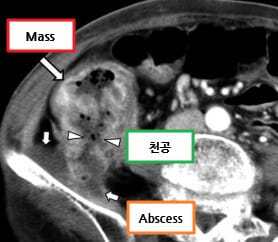

CT 소견 (Contrast-enhanced CT)

🔵 주위 지방 침윤

장 주변 지방조직에 염증 또는 종양 침윤이 퍼지며 음영이 흐려지는 소견입니다.

Kim, S. W., Shin, H. C., Kim, I. Y., Kim, Y. T., & Kim, C.-J. (2010). CT findings of colonic complications associated with colon cancer. Korean Journal of Radiology, 11(2), 211–221. https://doi.org/10.3348/kjr.2010.11.2.211